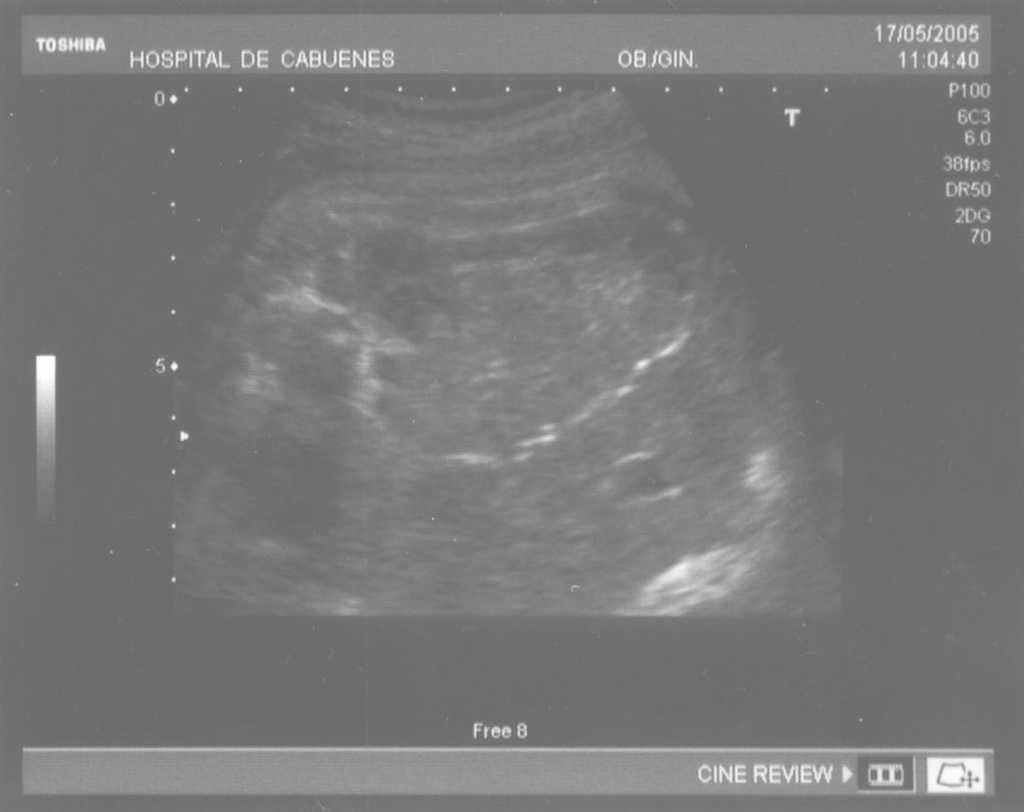

Las calcificaciones peritoneales son el hallazgo más consistente de PM y de hecho es la referencia en todas las series para establecer el diagnóstico posnatal en la radiografía simple de abdomen. Sin embargo, los criterios diagnósticos prenatales de PM no son uniformes y no se aplican de la misma manera por todos los autores. Las calcificaciones aparecen entre el 0-100% de los casos y en nuestra revisión, excluida la serie de Eckoldt et al8, en el 71,8%. Chan et al13 exigen como criterios para diagnóstico de PM la presencia de ascitis más dilatación de asas intestinales o calcificaciones. Sólo encuentran calcificaciones en 1/7 casos y argumentan que pueden pasar inadvertidas a los ultrasonidos. Eckoldt et al8, en una serie de 11 casos, no describen calcificaciones en ninguno y añaden: «no es común en nuestra institución practicar rayos X a la mujer gestante», e incluyen como diagnóstico prenatal de PM un caso con sólo ascitis, dos con ascitis e intestino ecogénico y dos con ascitis y polihidramnios, criterios que parecen insuficientes para establecer el diagnóstico de PM, aunque sea confirmado posnatalmente. Kamata et al23 sólo encuentran calcificaciones en 5/20 casos. Otros casos aislados comunicados tampoco encuentran calcificaciones1,10. El estudio de Dirkes et al14, citado en todas las comunicaciones por su clasificación de la PM en función del probable pronóstico neonatal, comunica calcificaciones en 9/9 casos y manifiestan: «el más frecuente y consistente hallazgo ecográfico, que es virtualmente patognomónico de PM, es la presencia de calcificaciones intraabdominales descartando su origen biliar, vascular, intraluminal, de órgano sólido o calcificación tumoral (...) la ascitis fetal aislada, la dilatación intestinal o el polihidramnios no son suficientes para el diagnóstico de PM». Chalubiski et al5 encuentran calcificaciones en algún momento del seguimiento prenatal en 8/9 casos y lo consideran el hallazgo más frecuente; Shyu et al12, en 16/17 casos; Tseng et al24, en 15/19 casos, y Foster et al4, en 6/7 casos y revisan los 19 casos comunicados previamente de diagnóstico prenatal de PM y encuentran calcificaciones o masas ecogénicas en 16/19 casos. Estroff et al6 comunican calcificaciones en 3/3 casos; éstas también están presentes en numerosos casos aislados1,3,7,25-27. Conviene tener presente que las calcificaciones abdominales encontradas en la PM son de localización peritoneal (extendidas por la superficie peritoneal) y deben distinguirse de las calcificaciones parenquimatosas, limitadas al parénquima hepático y, menos frecuentemente, al esplénico28. Aunque las calcificaciones peritoneales suelen ser más difusas, más numerosas y más groseras (como el caso que describimos; fig. 1) no debe obviarse este diagnóstico diferencial, de mayor importancia cuando la calcificación es el único hallazgo y de mayor dificultad cuando son escasas o se asocian con polihidramnios, pues en estas ocasiones no debemos pasar por alto la posibilidad de infección fetal u otras etiologías29. Además, debido al gran tamaño del hígado fetal, en ocasiones puede ser difícil localizar con precisión si las calcificaciones son peritoneales o hepáticas30. Sugieren una localización peritoneal: a) las calcificaciones que respetan el parénquima hepático y esplénico y se localizan en sus márgenes; b) la formación de láminas que «perfilan» el diafragma, y c) la localización en el escroto de un feto varón, que son particularmente diagnósticas de PM, debido a la conexión del saco escrotal con la cavidad peritoneal a través del proceso vaginal. Estos hallazgos estuvieron presentes en el caso que describimos (figs. 2, 3 y 4). Más raramente se localizan en el tórax por comunicación a través de los hiatos de la cava, la aorta o el esófago31. Debe tenerse presente la localización escrotal para establecer el seguimiento, pues no es inusual que en los primeros meses neonatales den lugar a masas o un escroto agudo que requieren intervención quirúrgica; la dificultad para orientar el diagnóstico es mayor cuando falta el antecedente de PM prenatal32-38.

Figura 3. Calcificaciones formando «láminas» que perfilan el diafragma.